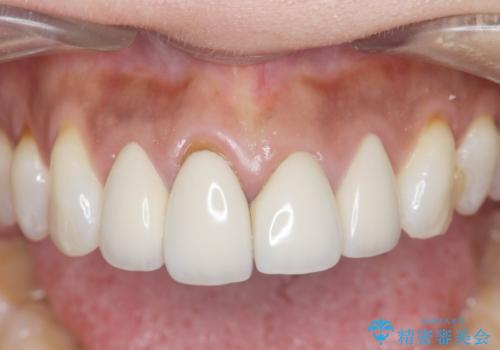

見た目が自然になり、色調も天然の歯とおなじような透明感のある色調が再現され、大変喜んでいただくことができました。